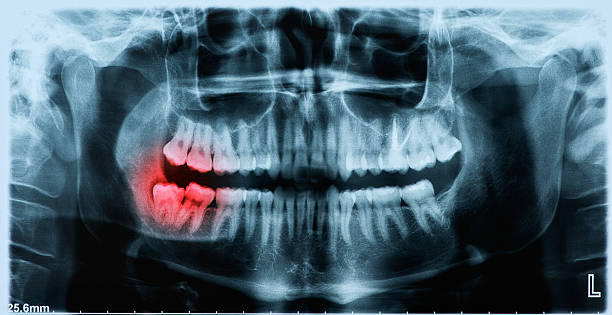

Impacted Wisdom Teeth Symptoms You Shouldn’t Ignore

July 01, 2025

An impacted wisdom tooth doesn’t just sit quietly. It can cause pain, infections, and even damage to nearby teeth or bone. Knowing the symptoms of impacted wisdom teeth can save you from bigger oral health issues later.